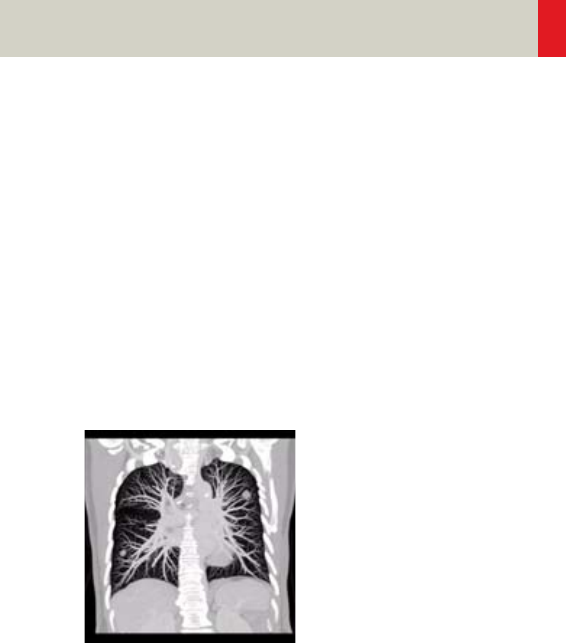

Thorax 226

•Overview 226

- General Hints 229

- Body Kernels 231

•Scan Protocols 232

- ThoraxRoutine/

ThoraxRoutine06s 232